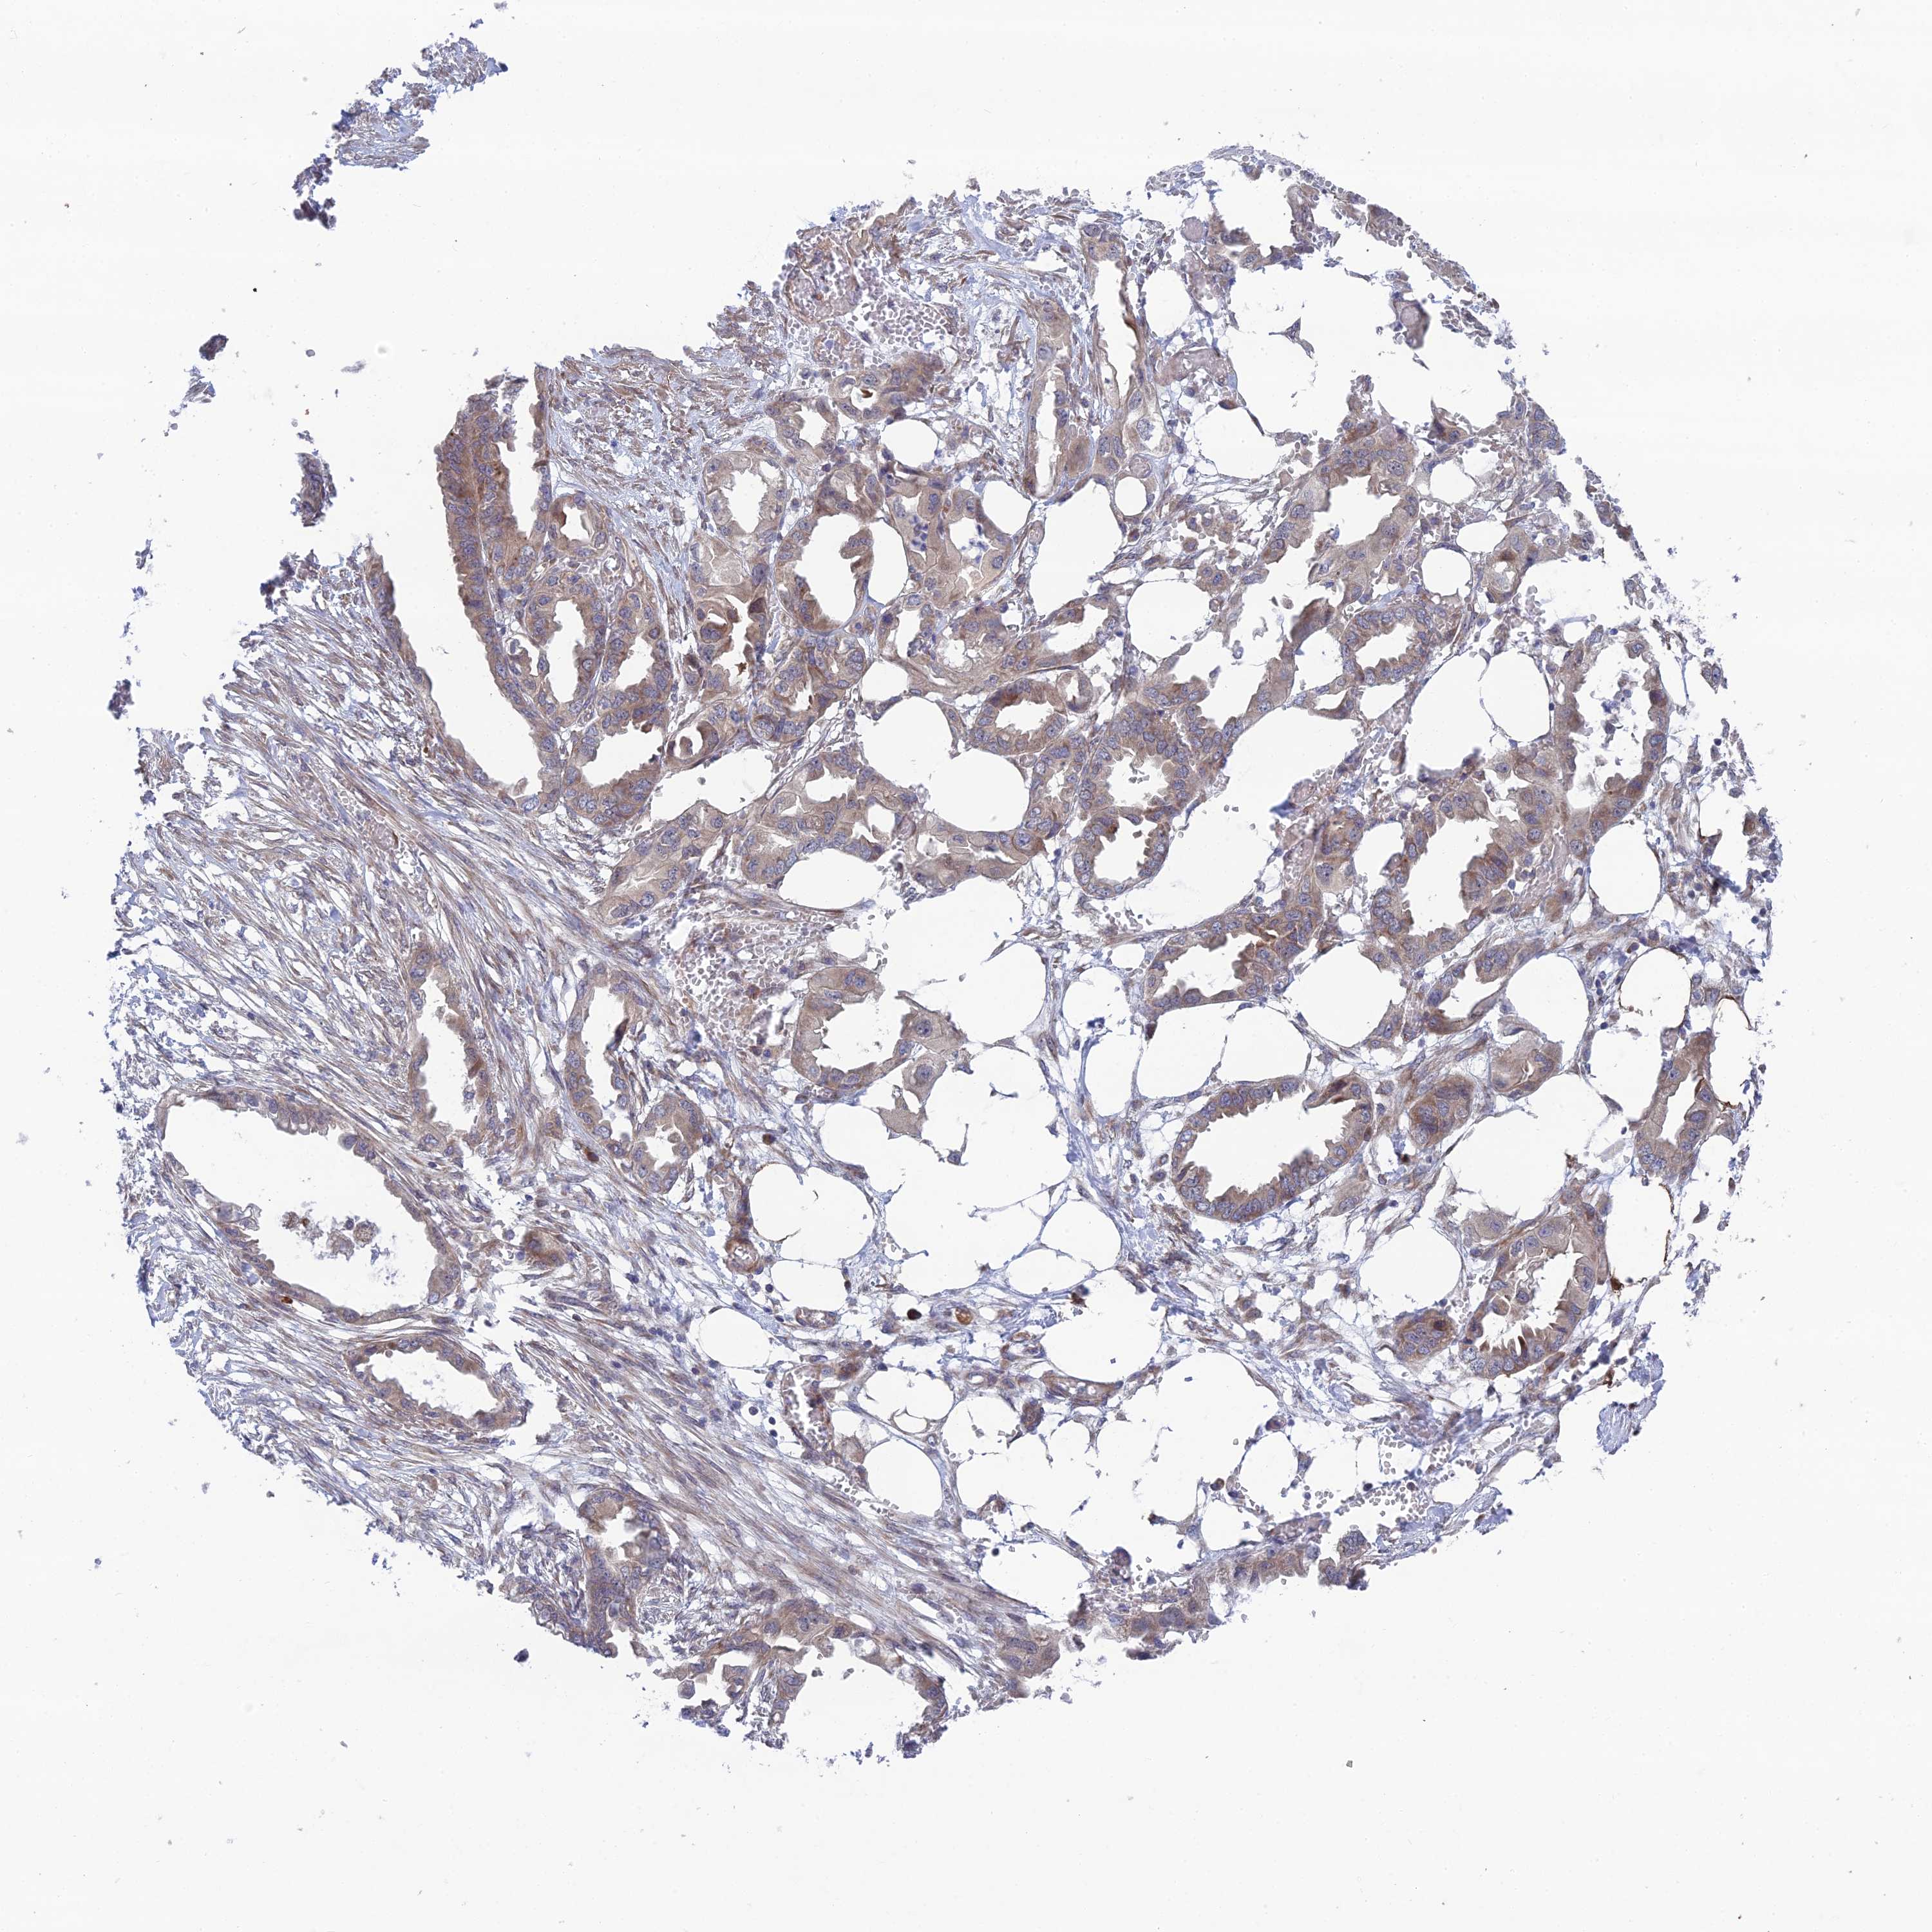

ENDOMETRIAL CANCER - Protein expressioni

A mouse-over function shows sample information and annotation data. Click on an image to view it in a full screen mode. Samples can be filtered based on level of antibody staining by selecting one or several of the following categories: high, medium, low and not detected. The assay and annotation is described here.

Note that samples used for immunohistochemistry by the Human Protein Atlas do not correspond to samples in the TCGA dataset.

Antibody stainingi

Antibody staining in the annotated cell types in the current human tissue is reported as not detected, low, medium, or high, based on conventional immunohistochemistry profiling in selected tissues. This score is based on the combination of the staining intensity and fraction of stained cells.

Each image is clickable and will lead to virtual microscopy that enables deeper exploration of all samples and also displays staining intensity scores, fraction scores and subcellular localization as well as patient and tissue information for each sample.

Antibody HPA044359

Staining

High

Medium

Low

Not detected

Intensity

Strong

Moderate

Weak

Negative

Quantity

>75%

75%-25%

<25%

None

Location

Nuclear

Cytoplasmic/membranous

Cytoplasmic/membranous,nuclear

Adenocarcinoma, NOS

Adenocarcinoma, metastatic, NOS